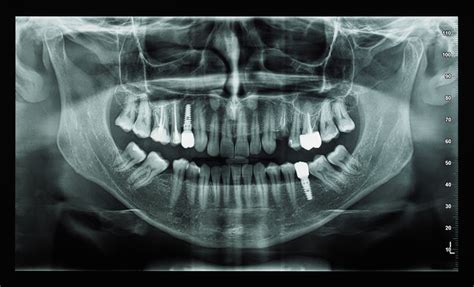

Las máquinas de rayos X dentales son ampliamente utilizadas en odontología. El equipo está diseñado para la pronta recuperación de imágenes de pacientes con dientes, tanto para el diagnóstico y diagnóstico, como en el proceso de procedimientos terapéuticos e intervención quirúrgica. La industria dental está en constante desarrollo y se caracteriza por una serie de tendencias pronunciadas. Uno de ellos es el funcionamiento de los sistemas de visualización en el proceso de proporcionar una atención médica eficaz a los pacientes.

Las máquinas de rayos X dentales se distinguen por el tipo de registrador. A diferencia de la unidad clásica de rayos X, las unidades dentales tienen diseño ergonómico, bajo peso y alta velocidad de operación. Con su ayuda usted puede obtener rápidamente una imagen.

- Equipo analógico: Con un tipo de película de la grabadora es más barato. Proporciona alta calidad de la imagen final, pero irradia más al paciente. La imagen se aplica a la película de rayos X, que requiere ciertos costos de material y tiempo.

- Radiovisiógrafos digitales: Son más caros, pero al instante forman una imagen con buenos detalles. Preste atención a los equipos que soportan el trabajo con el radiovisiógrafo y la sincronización con el ordenador.